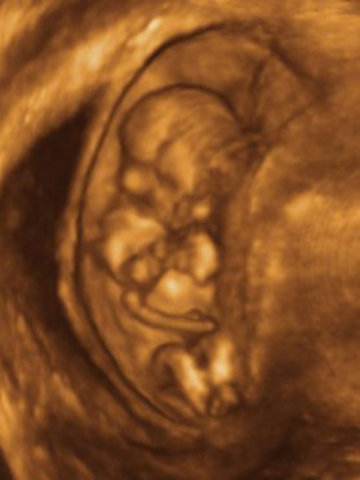

• Month 3

Month 3

-Breasts become firmer and fuller,may ache.

-Nausea,fatigue,and frequent urination may continue

-Abdomen becomes slightly larger.The uterus is about the size of an orange

• Month 4

Month 4

-abdomen continues to grow slowly.

-Most discomforts of early pregnancy,such as morning sickness, usually gone.

-Appetite increases